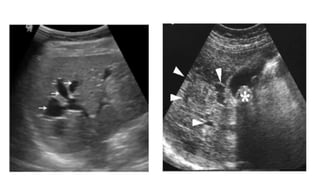

USG

• Ballooned/fusiform cyst beneath porta hepatis separate from GB

• *Communication with bile duct needs to be demonstrated*

• Abrupt change of caliber at junction of dilated segment to normal

ducts

• Intrahepatic bile duct dilatation secondary to stenosis.

USG • Ballooned/fusiform cystbeneath porta hepatis separate from GB • *Communication with bile duct needs to be demonstrated* • Abrupt change of caliber at junction of dilated segment to normal ducts • Intrahepatic bile duct dilatation secondary to stenosis.